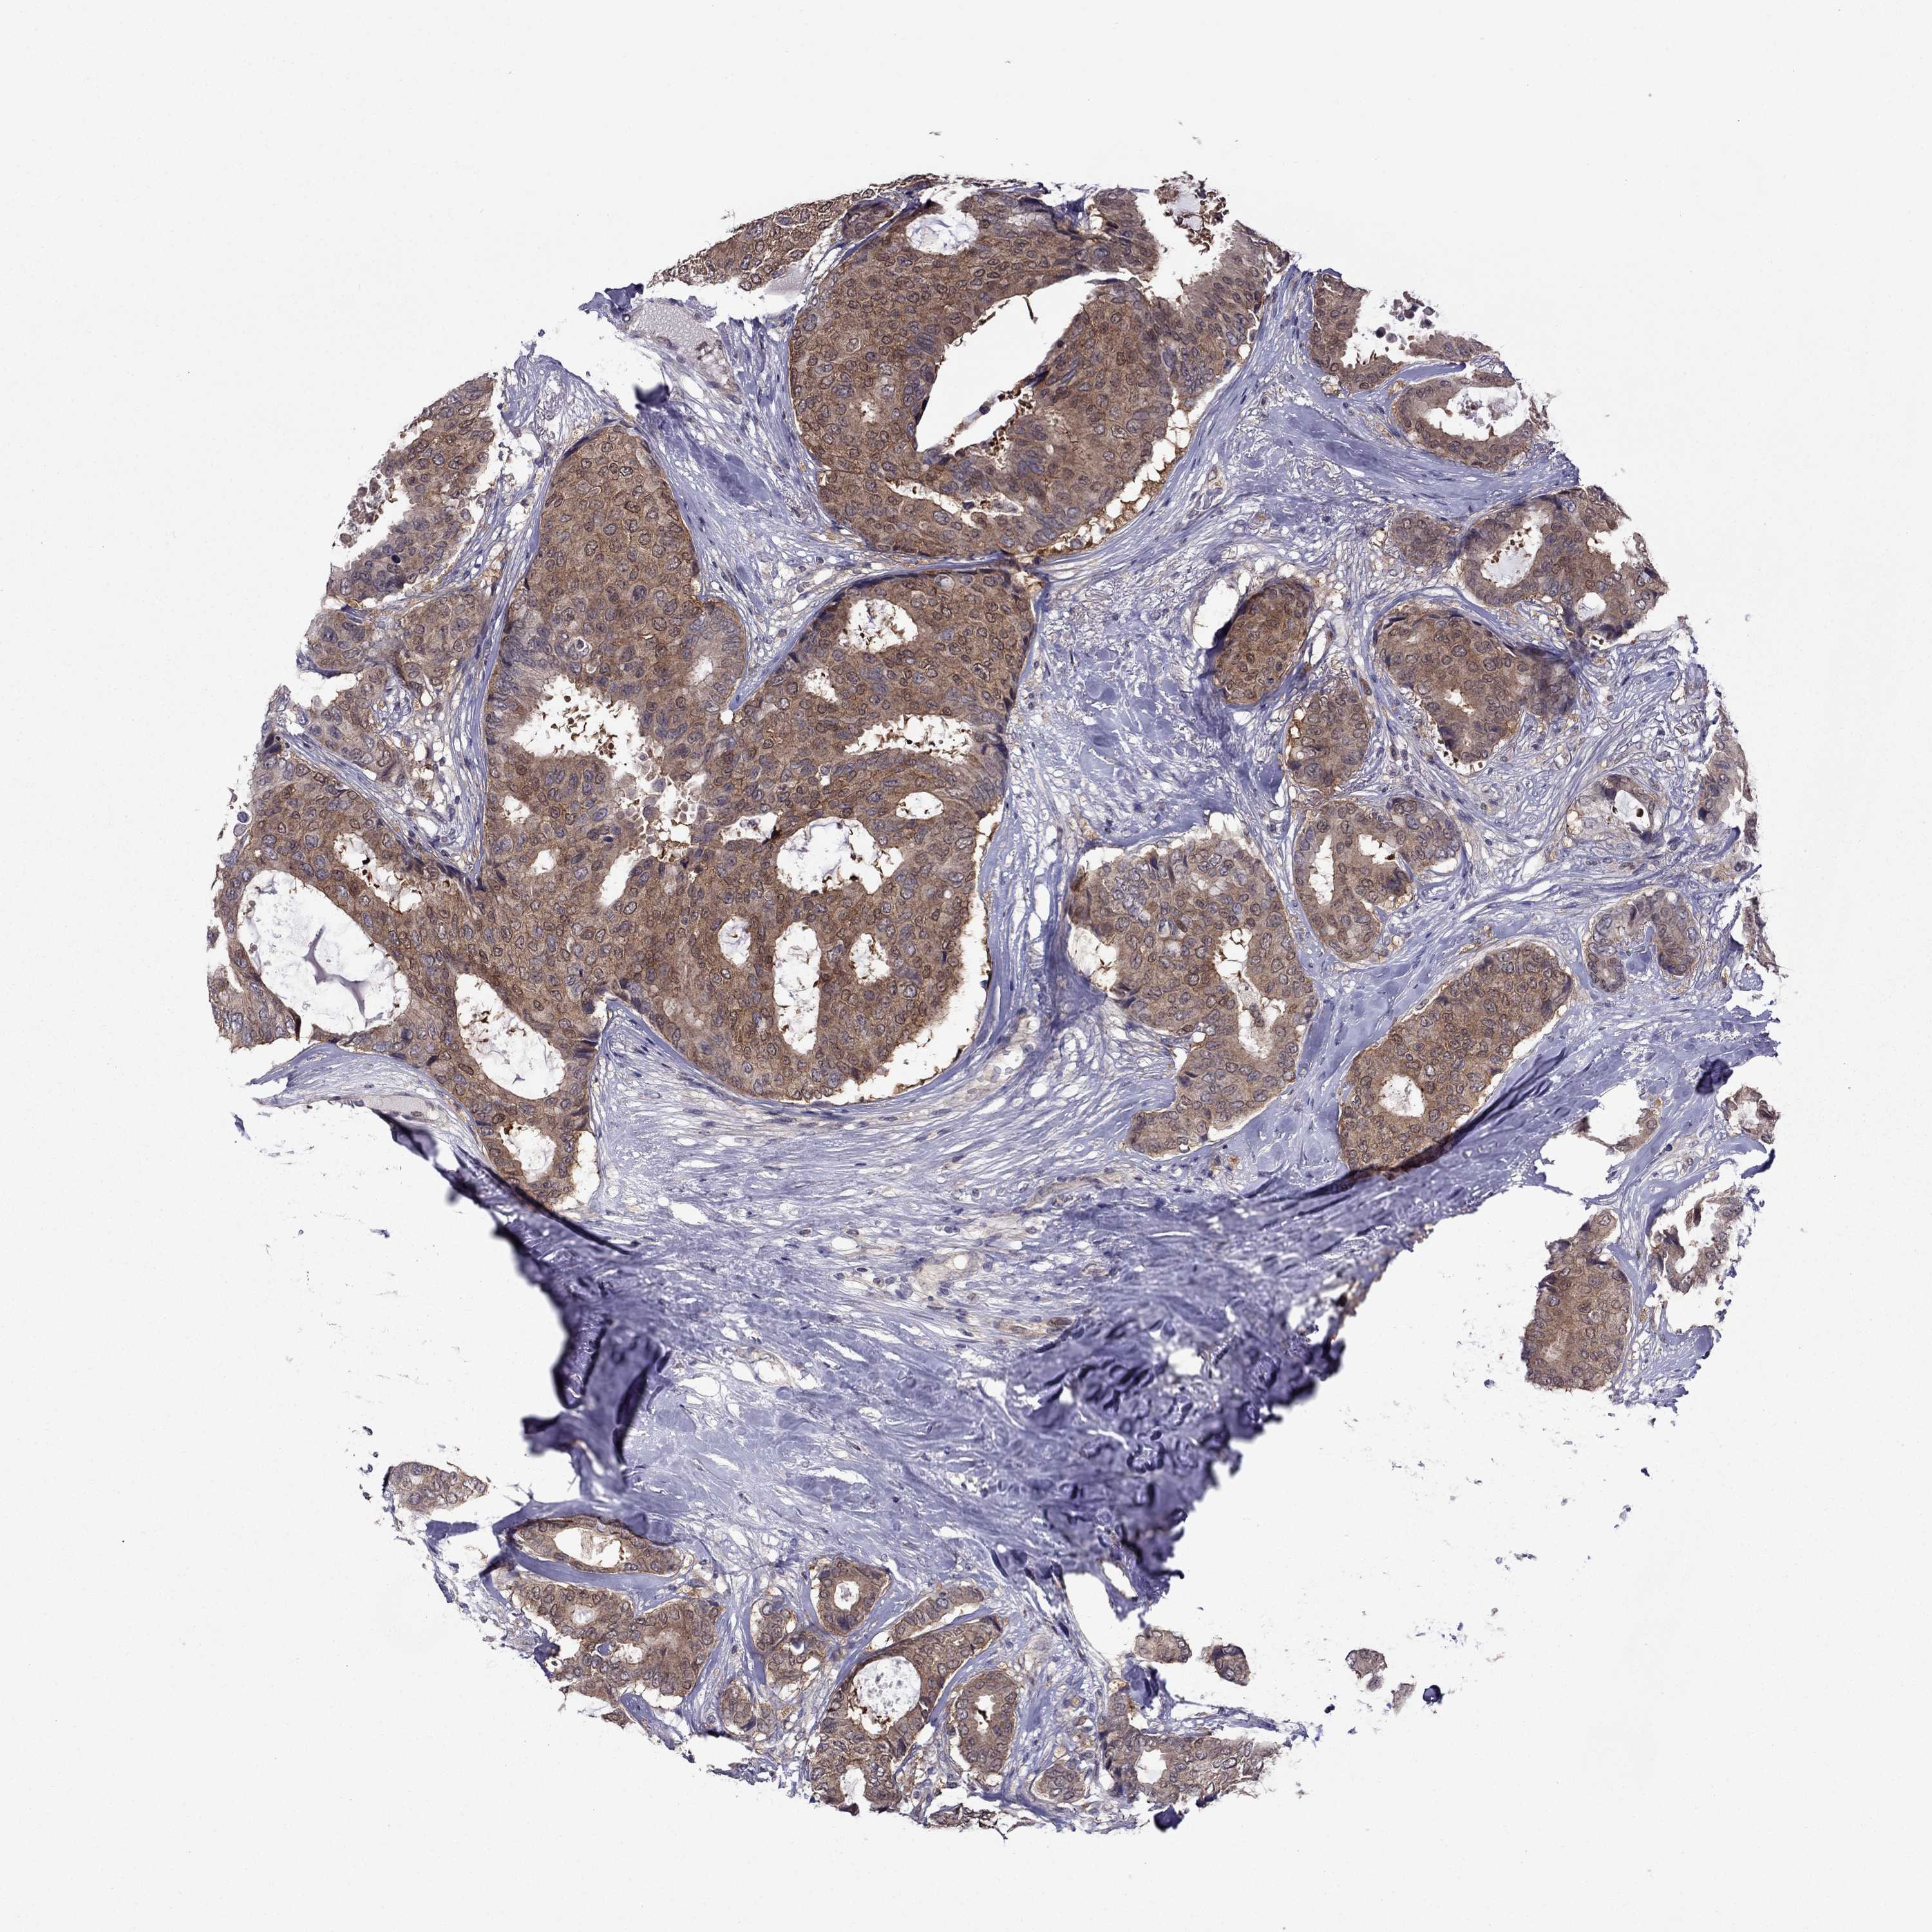

CANCER BREAST CANCER Show tissue menu

BRCA TCGA BRCA VALIDATION PROTEIN EXPRESSION